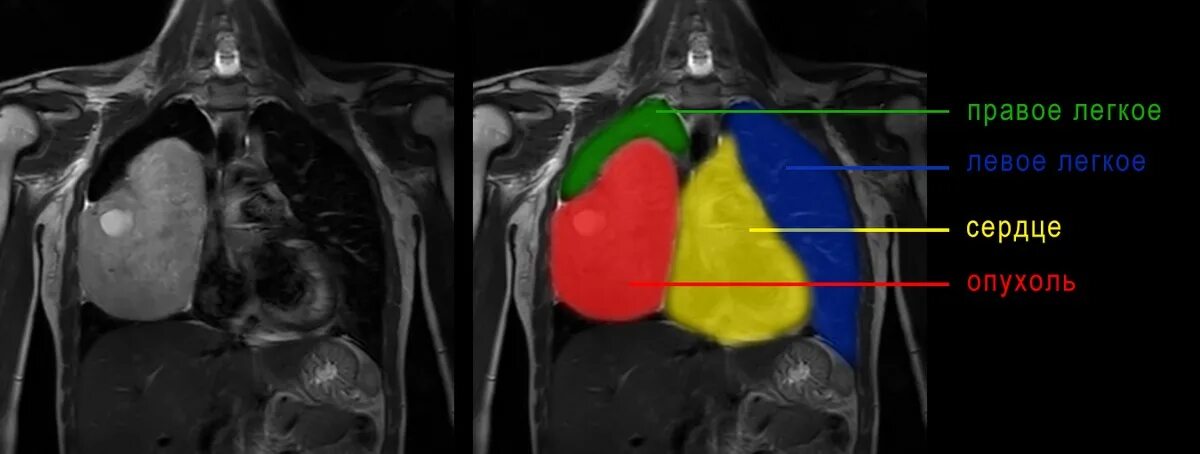

Метастазы в средостении легких